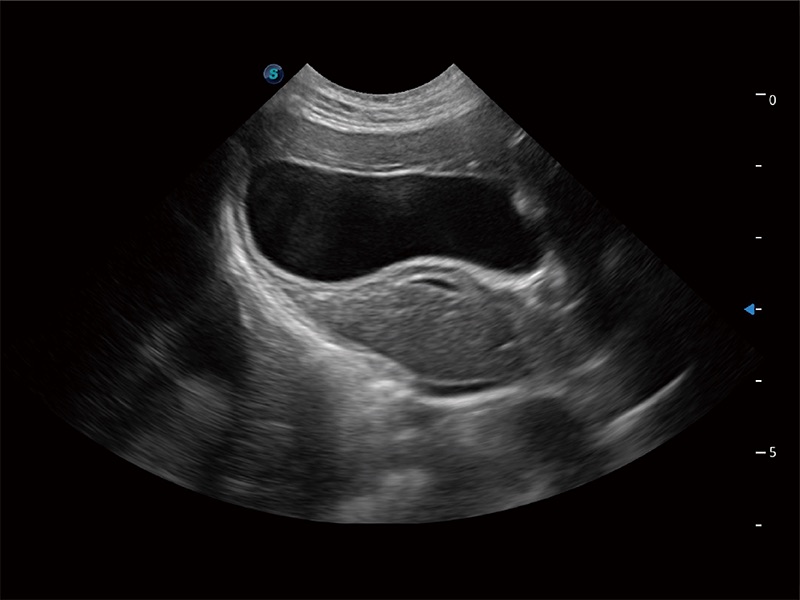

动物是人类最亲密的朋友和最值得信赖的伙伴。米兰官方网站也一直致力于探索动物专用的超声影像解决方案。全新推出的ProPet系列,是米兰官方网站在动物超声影像智能化、专业化、精准化的一次跨越式革新。动物不能用言语来表述自己的不适,通过超声影像,ProPet系列搭建了动物医生与不同物种沟通的“桥梁”,为动物医生注入了“治愈之力”。 ProPet 80 是米兰官方网站匠心打造的一款高端动物专用彩超,采用性能卓越的全新硬件架构,极大提升超声系统的运行效率和数据处理能力,帮助动物医生从容应对日益增多的挑战性病例和日益多样化的临床需求。

高性能和先进的临床应用工具可以为动物医生提供临床信心。ProPet 80 搭载了先进的腹部和浅表应用工具,帮助医生在日常临床实践中发挥前所未有的作用。

ProPet 80 全新的动物超声智能软件和丰富的探头群,为动物医生提供了高清晰度和精细分辨率的图像,无论在宠物、马科、畜牧还是实验室动物等应用中都可以轻松应对,为您的日常工作带来满意的体验。